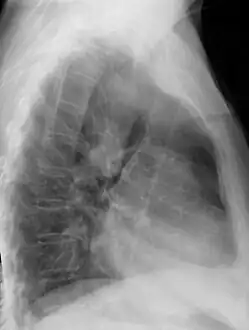

Chest radiograph showing a right-sided aortic arch, lateral view

After birth, a right-sided aortic arch is visualized on chest radiography, by the aortic knob (the prominent shadow of the aortic arch) that is located right from the sternum instead of left. Complex lesions are often assessed by MRI or CT.